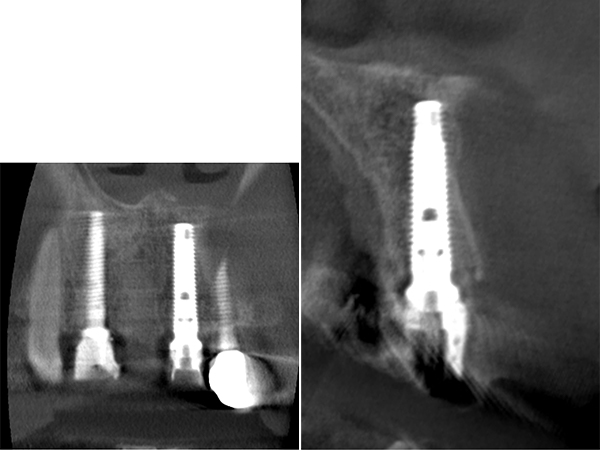

デンタルレントゲン写真

右上1番と2番、左上1番の根の先には大きな病変(レントゲン上で黒く写っている部分)が確認できました。右上1番と2番に関しては、15年ほど前に歯根端切除を行っているとのことより、再手術を行うと現状よりもさらに歯根が短くなってしまい、歯の揺れが大きくなることが予想されました。

右上1番と2番、左上1番の根の先には大きな病変(レントゲン上で黒く写っている部分)が確認できました。右上1番と2番に関しては、15年ほど前に歯根端切除を行っているとのことより、再手術を行うと現状よりもさらに歯根が短くなってしまい、歯の揺れが大きくなることが予想されました。

CTを撮影し、歯根の長さや根尖病変の大きさを精査しました。

1次手術手術後のレントゲン写真

2|

|1

レントゲン写真による評価